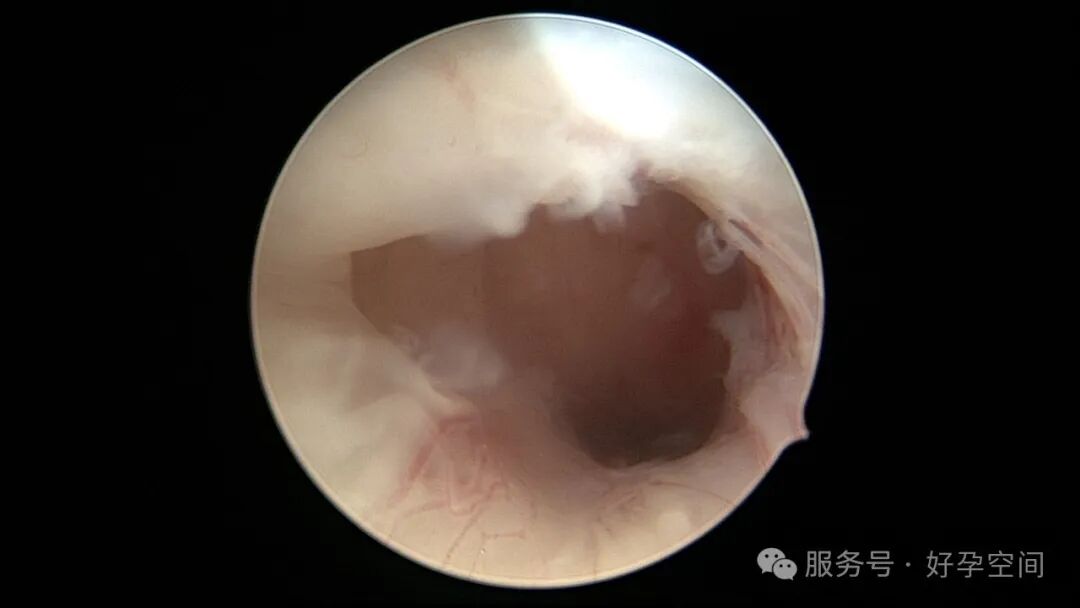

输卵管吻合术后妊娠,稽留流产,清宫术后宫腔粘连,宫腔镜单极电针分粘

分粘后宫腔镜二探,残留少许膜性粘连,镜鞘分粘

试管前宫腔镜检查